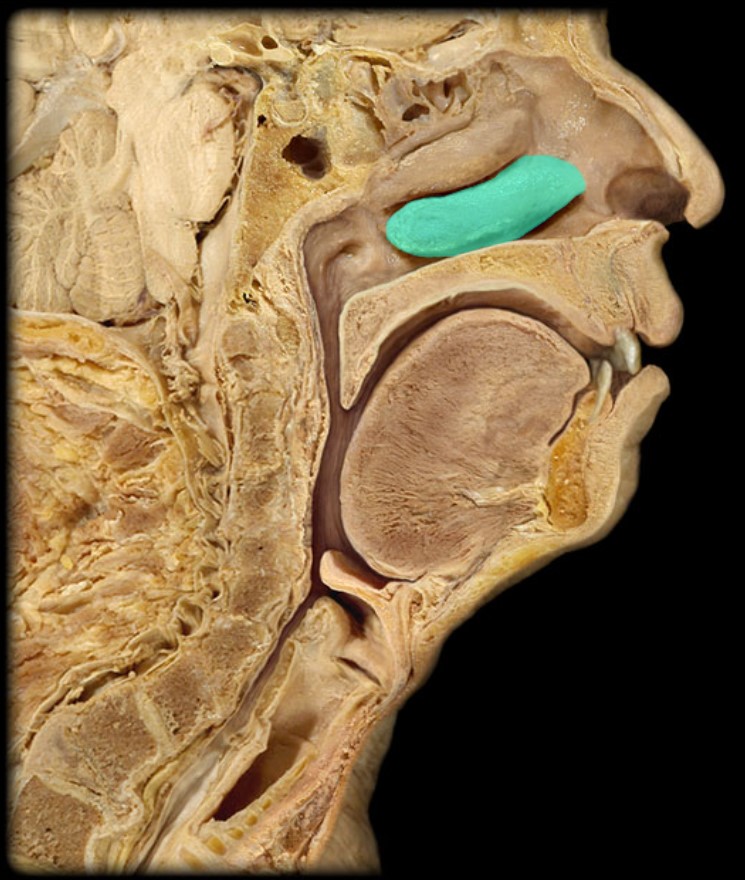

Soft Palate

Palatine Bone

Maxilla

Pharyngeal Tonsil

Torus Tubarius

Sphenoid Sinus

Inferior Nasal Concha

Middle Nasal Concha